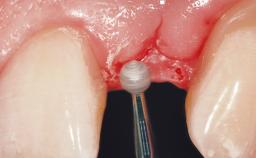

Early (Type 2) placement in a healthy, non-smoking male patient aged 28 years who required removal and replacement of the maxillary right central incisor due to external root resorption. A horizontal bone deficit requires a simultaneous augmentation procedure. The overall esthetic risk is high due to the horizontal bone deficit, medium to high lip line with exposure of the soft tissue margin when smiling, and the patient’s high esthetic expectations.

After flapless tooth extraction and a healing period of 6 weeks, a standard-diameter one-piece implant is placed. A gap between the implant and the facial bone wall is filled with autogenous bone chips harvested from the anterior nasal spine and covered with DBBM particles. Contour augmentation on the facial aspect is achieved using DBBM particles and a collagen membrane, according to the principles of guided bone regeneration (GBR). The flap is coronally repositioned for semisubmerged healing.